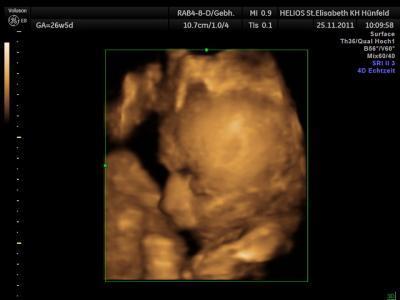

Morgen haben wir wieder CTG und VU. Sind schon ganz gespannt und hoffen, das alles gut ist und es unserem Prinzen gut geht!!!! Und nach dem FA gehts dann auf den Weihnachtsmarkt sofern das Wetter mitspielt :D *FREU* Und am Sonntag ist dann bei uns Weihnachtsmarkt - dritter Advent und wir haben dann auch endlich die 3 davor stehen ;D Euch allen noch einen wunderschönen Abend :-) VLG. Änni, Oli und klein Eric im Bauchi

Bild zu Morgen wieder VU und Sonntag dann endlich die 3 davor :D - Forum für Februar - Mamis